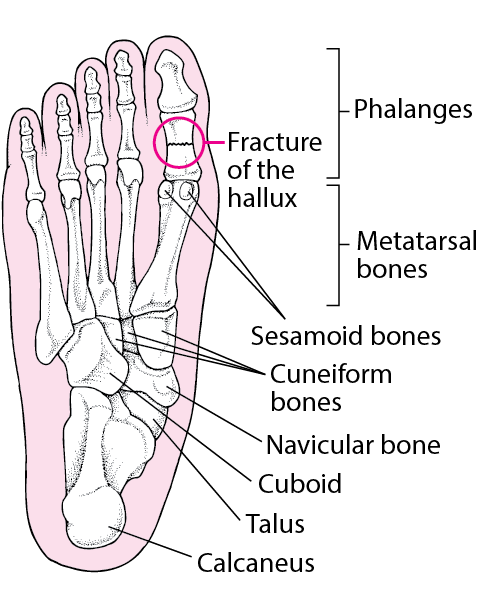

phalanges fracture